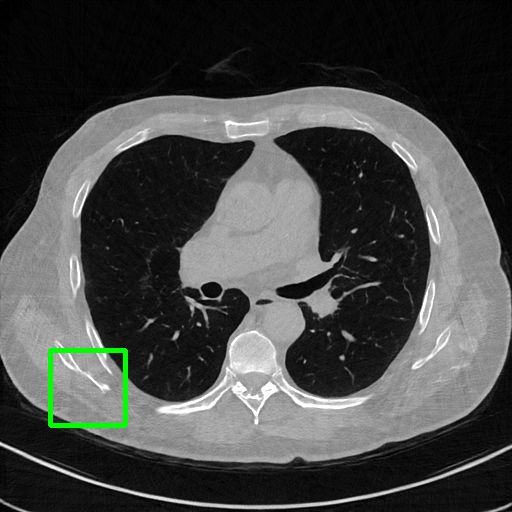

Qualitative comparison. We also visualize the reconstructed images of these methods in Fig. 4 with = [72, 96 ,144] (See more visualizations in Appendix). In all three rows, our DuDoTrans shows better detail recovery, and sparse-view artifacts are suppressed. Further, when decreasing , where raw sinograms are too messy to be restored and low-quality images from FBP are too hard to capture global features, Transformer-based models exhibit reduced performance. The phenomena suggests that we should design suitable structures with the Transformer and CNNs, facing with different cases.

Ground Truth

FBP

FBPConvNet

DuDoNet

ImgTrans

DuDoTrans